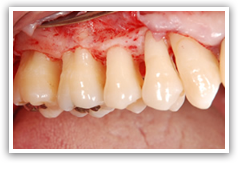

読んで字のごとく外科治療になります。歯周病最大の原因と言える歯肉縁下歯石は歯周ポケットの中に存在するので直視下で除去することはできません。手の感覚でその位置を探り除去しているので、取り残しは必ずと言っていいほど起きてしまいます。多少の取り残しがあっても通常の歯石量や歯周病の進行度であればそれが原因で歯周病が悪化したりは起こりませんが、もともとの歯石が多かったり、すでに歯周病がかなり進行してしまっている場合は取り残しをさらに少なくしなければなりません。

歯ぐきをメスで切り、一度はがして中をむき出しにすることで、直視下にて歯石除去が可能になり、SRP後わずかに取り残した歯石も取りきることができます。